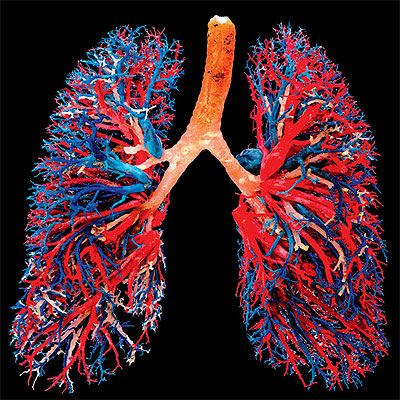

这里是它看起来的样子:

进一步的实验还揭露出大量以前隐藏的血液干细胞和巨核细胞的先驱细胞(progenitor cell,产生巨核细胞和红血球的细胞),就位在肺组织外部,每只老鼠的肺大概有1百万个。

当研究人员追踪巨核细胞的整个’生命周期’时,发现它们可能源自于骨髓,然后依它们的路径进入肺里,在那里开始制造血小板。